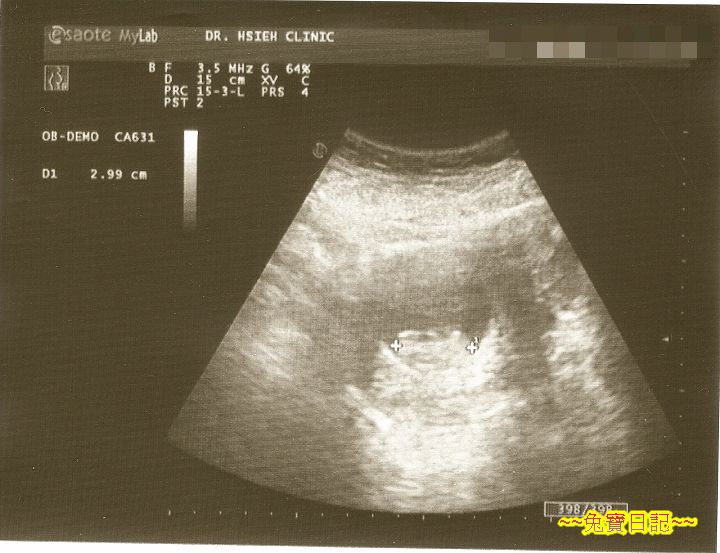

陳醫師問明情形後, 先做超音波檢查.

隨著醫師操作著超音波探頭, 螢幕上的畫面閃過一個又一個模糊的影像, 看醫生量得專心, A 大氣也不敢喘一下.

這時醫生說話了, 胎兒一切正常, 心跳約每分鐘 140 下, 身長約 3 公分, 很正常感覺也很健康. 暫時不用擔心.